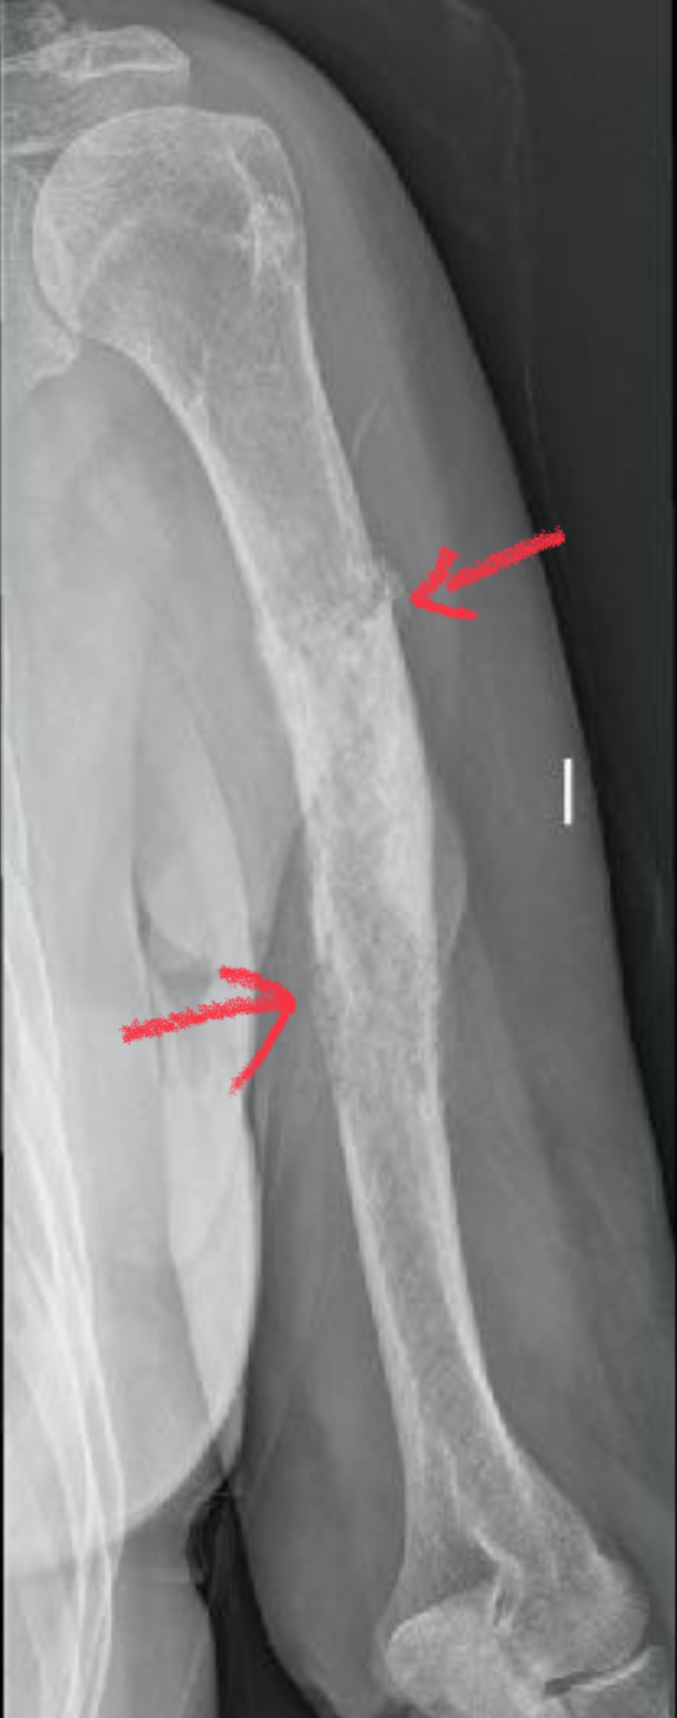

La resección del osteosarcoma con márgenes negativos es el paso clave para erradicar el tumor. En este caso vemos un osteosarcoma de femur.

Osteosarcoma

Osteosarcoma femur

Debemos realizar los cortes en el femur siguiendo las líneas azules, dejando el área verde de seguridad (márgenes negativos) y lejos del area roja donde se encuentra el osteosarcoma